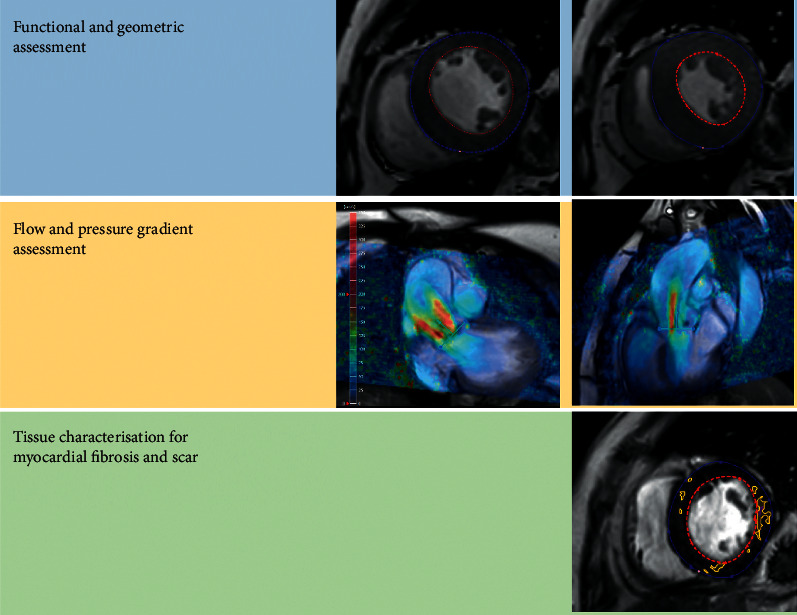

心血管磁共振成像(CMR)对了解各种疾病的过程和病理生理机制产生了巨大影响。最近,它对瓣膜性心脏病患者的诊断和风险分层做出了重大贡献。随着 CMR 的应用越来越广泛,它可以对左心室容积和质量进行详细、可重复、定性和定量的评估,从而评估瓣膜病变对心肌的血流动力学影响。利用特征跟踪 CMR 方法对常规获取的图像进行后处理,可获得有关心肌变形和应变参数的宝贵信息,这些信息表明存在亚临床心室损伤,而射血分数(EF)等传统测量方法仍无法检测到这些损伤。由于越来越多的证据表明纤维化的存在与不良事件和预后有关,因此 T1 图谱和晚期钆增强 (LGE) 成像可提供深层心肌组织特征,从而改变了对患者进行风险分层的方法。本综述总结了目前有关 CMR 在主动脉瓣狭窄或二尖瓣反流患者左心室评估中的作用及其在诊断、风险分层和管理中的价值的证据。

Cardiovascular magnetic resonance (CMR) imaging has had a vast impact on the understanding of a wide range of disease processes and pathophysiological mechanisms. More recently, it has contributed significantly to the diagnosis and risk stratification of patients with valvular heart disease. With its increasing use, CMR allows for a detailed, reproducible, qualitative, and quantitative evaluation of left ventricular volumes and mass, thereby enabling assessment of the haemodynamic impact of a valvular lesion upon the myocardium. Postprocessing of the routinely acquired images with feature tracking CMR methodology can give invaluable information about myocardial deformation and strain parameters that suggest subclinical ventricular impairment that remains undetected by conventional measures such as the ejection fraction (EF). T1 mapping and late gadolinium enhancement (LGE) imaging provide deep myocardial tissue characterisation that is changing the approach towards risk stratification of patients as an increasing body of evidence suggests that the presence of fibrosis is related to adverse events and prognosis. This review summarises the current evidence regarding the utility of CMR in the left ventricular assessment of patients with aortic stenosis or mitral regurgitation and its value in diagnosis, risk stratification, and management.